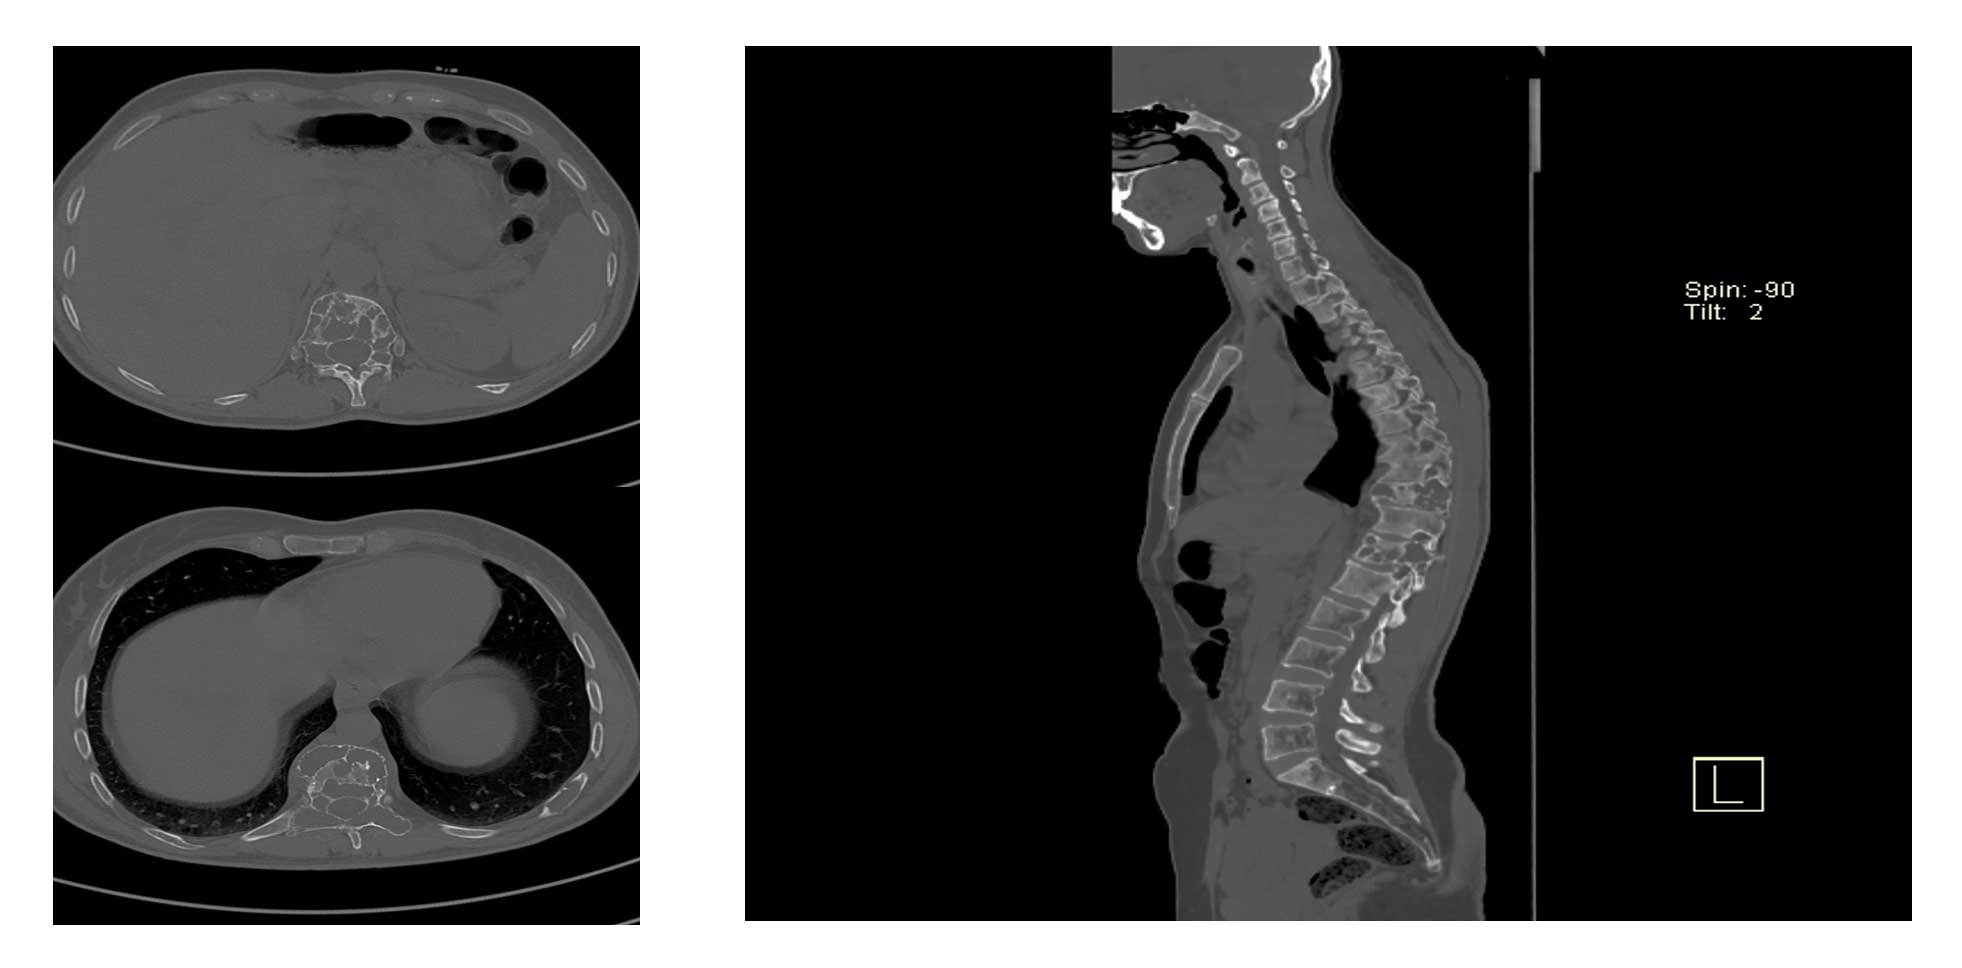

Ameliyat Öncesi: MR’da kemiğin içini tamamen dolduran kistik lezyon görülmekte.

Ameliyat Öncesi: Tomografide iki farklı seviyede harabiyete ve çökme kırığına neden olan kistik lezyonlar görülmekte.